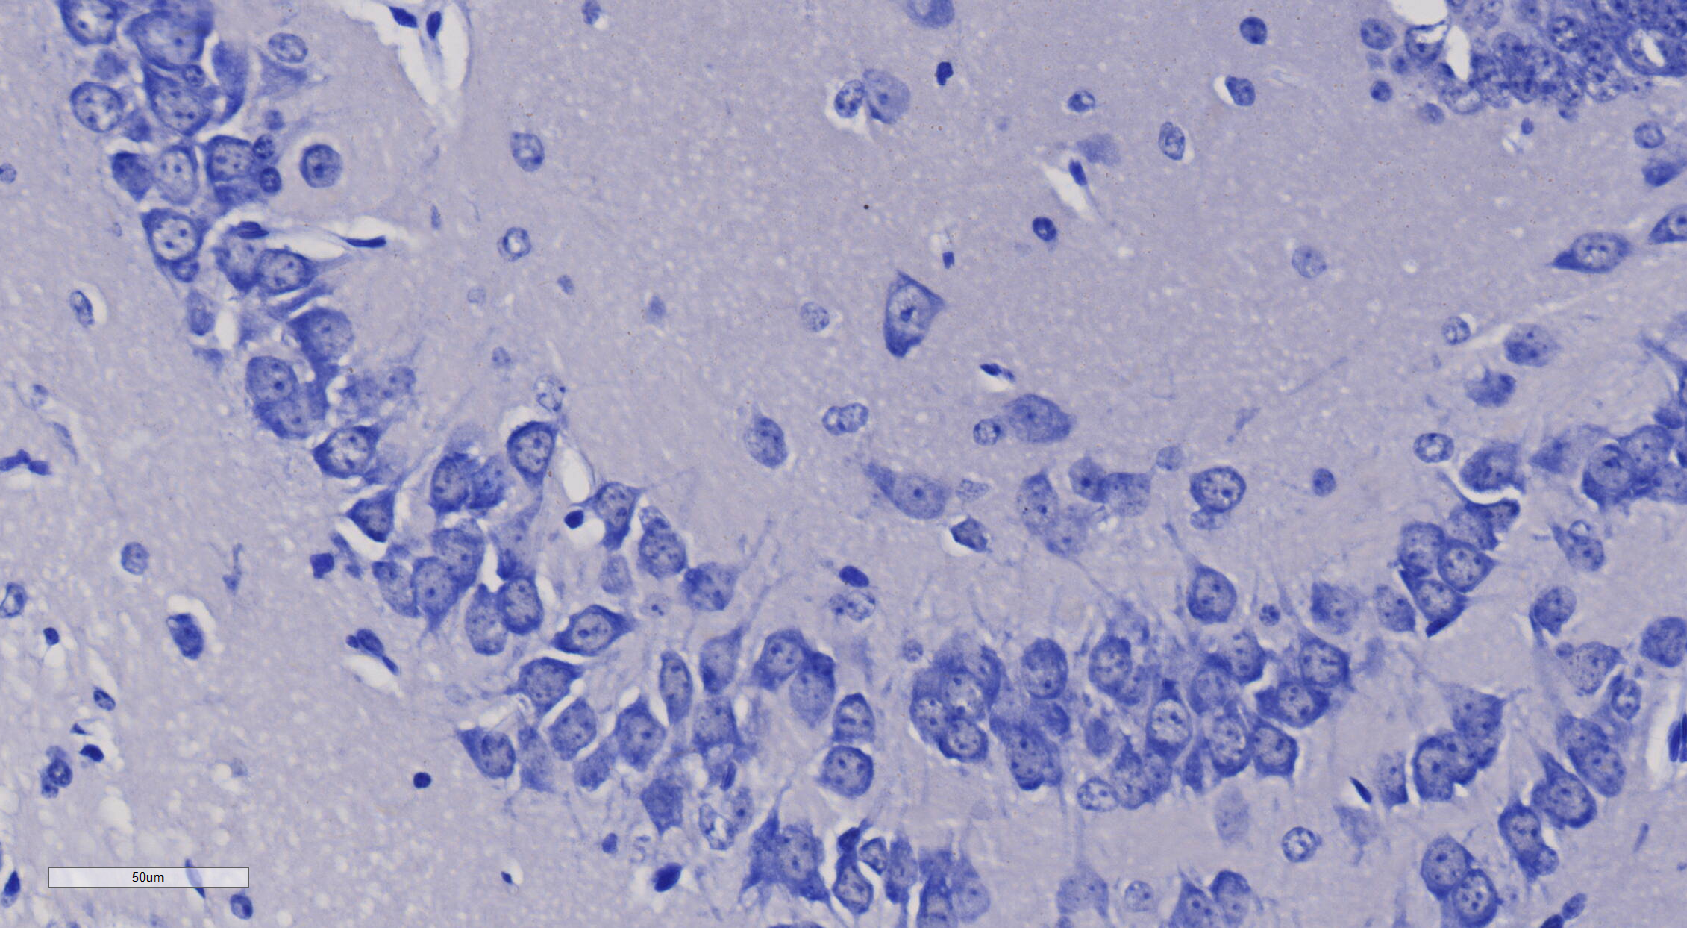

尼氏染色

小鼠脑部整体尼氏染色 海马结构 尼氏小体